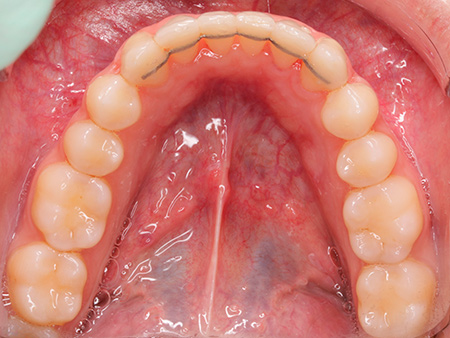

Aunque Ana no tenía un problema grave de mordida, acudió a Ferrus & Bratos para mejorar su estética dental. Sus dos incisivos -superior e inferior- no estaban en la posición adecuada y notaba cómo se iban desplazando, afectando a su sonrisa. Ana se puso en manos de la doctora Patricia Bratos, quien le recomendó un tratamiento con Invisalign para corregir su dentadura sin que ello afectara a su apariencia.

Después de extraer sus dos cordales superiores para conseguir mayor espacio en la boca, Ana comenzó su tratamiento, que tuvo una duración de 19 meses. Nuestra paciente asegura que los efectos han sido muy positivos y enseguida se acostumbró a llevar las férulas transparentes. Una vez finalizado su tratamiento, Ana observa cómo la expresión de su cara ha cambiado a mejor, pues sus dientes estás completamente alineados.